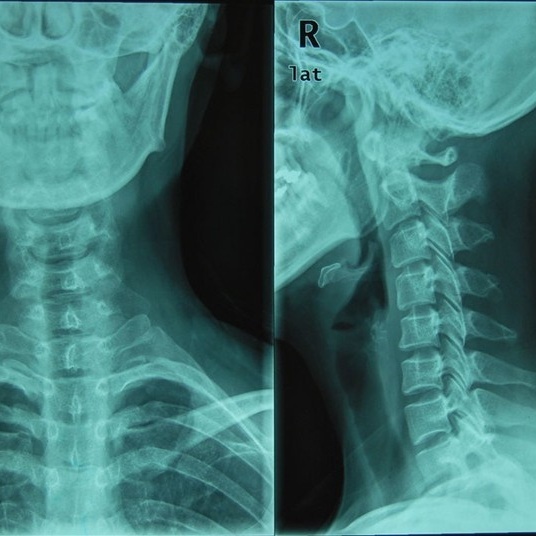

什么是颈椎反弓

颈椎反弓

生理性前凸,低头族的颈椎会逐渐向相反方向弯曲,出现"颈椎反曲""反弓"

什么是颈椎反弓?

颈椎反弓越来越常见严重还会引起瘫痪